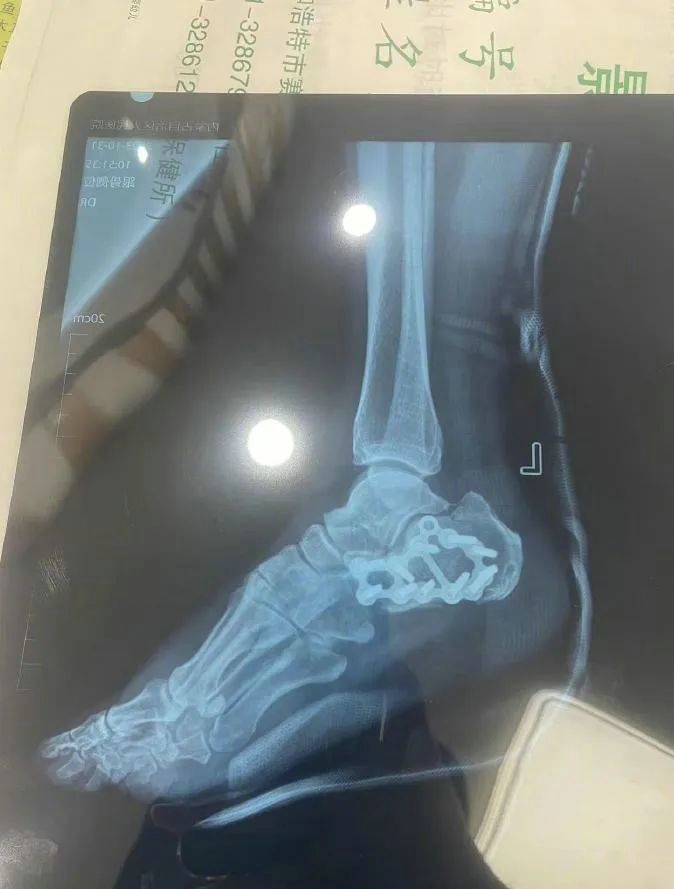

“那時(shí)候我剛工作了兩天,在第三天10月22日下午施工過程中從三層高的鐵架上摔了下來,導(dǎo)致30厘米左右的鋼筋刺穿我的右側(cè)臀部,左腳跟也粉碎性骨折,被送往內(nèi)蒙古自治區(qū)人民醫(yī)院救治,當(dāng)晚做了手術(shù)取出刺在右臀部的鋼筋,10月30日又進(jìn)行了左腳粉碎性骨折手術(shù)?!崩紫壬嬖V記者。

據(jù)雷先生介紹,當(dāng)時(shí)內(nèi)蒙古騰龍建設(shè)工程有限公司許經(jīng)理問過他賠付10萬元能否解決問題,他認(rèn)為這樣不太妥當(dāng)?!耙?yàn)槲业淖竽_骨折還要進(jìn)行二次手術(shù),并且我臀部受傷不能坐著,只能包車回家,會(huì)產(chǎn)生一系列的費(fèi)用?!崩紫壬f?! ?/p>

雷先生說他目前還在住院,左腳不能著地,生活也不能自理。內(nèi)蒙古騰龍建設(shè)工程有限公司的人也來過幾次,和他協(xié)商處理結(jié)果,但是始終沒有達(dá)成一致?!拔椰F(xiàn)在的訴求是想讓他們一次性賠償錢款,或者安排我去康復(fù)中心恢復(fù),具體按照他們的安排來。”